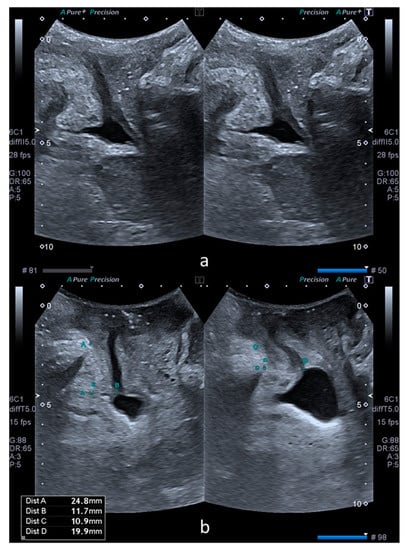

The bladder neck mobility was quantified by subtracting SPBN and DLM values at rest and on Valsalva, with the results being noted as ΔSPBN and ΔDLM. Subsequently, the rest, Valsalva and subtraction values of SPBN and DLM were compared between the cystocele and control groups. Figure 1 illustrates these parameters in a patient from the control group (a) and another patient from the case group (b).

Figure 1.

Comparative transperineal US images at rest (left) and on Valsalva maneuver (right). Image (a) was obtained from a patient without a cystocele. Image (b) was obtained from a patient with a cystocele. Image b also shows the measurements performed in the XY coordinate system. Dist A (left) and dist C (right) correspond to SPBN and dist B (left) and dist D (right) correspond to DLM.